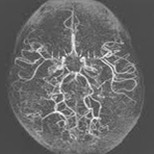

① 수술을 통해 새로운 혈류 경로를 충분히 확보하면, 뇌졸중 위험을 크게 줄이고 거의 정상적인 생활을 유지할 수 있습니다.

② 조기 진단 후 적절한 치료를 받은 환자는 장기적으로 매우 안정적인 경과를 보일 수 있습니다.

③ 꾸준한 추적 검사와 생활 관리로 발작 감소·인지기능 유지·일상 회복이 충분히 가능합니다.

즉, 완전한 치유는 어렵지만 “충분히 관리 가능한 만성 질환”이며, 대부분의 환자가 수술 후 학교·직장·일상생활로 정상 복귀하고 있습니다.

모야모야병은 드문 질환이지만 조기진단과 적절한 치료를 통해 충분히 관리할 수 있으며, 특히 뇌혈류를 회복시키는 우회술의 발전으로 환자의 삶의 질은 과거보다 매우 향상되었습니다. 중요한 것은 증상이 미묘해도 이를 가볍게 넘기지 않고 전문의의 평가를 받는 것이며, 가족력이 있는 경우에는 예방적 검사로 위험을 줄일 수 있습니다. 완치는 어렵지만 꾸준한 관리와 생활 습관 조절을 통해 장기적으로 안정된 생활을 유지하는 것이 가능합니다. 또한 아이와 성인 모두 스트레스·감염·탈수 등으로 증상이 악화될 수 있기에 평소 건강 관리가 무엇보다 중요합니다. 수술 후에도 정기적인 추적 관찰은 필수이며, 작은 변화도 즉시 확인하는 주의가 필요합니다. 결국 모야모야병은 두려운 병이 아니라, 제대로 알고 관리하면 충분히 함께 살아갈 수 있는 질환입니다.